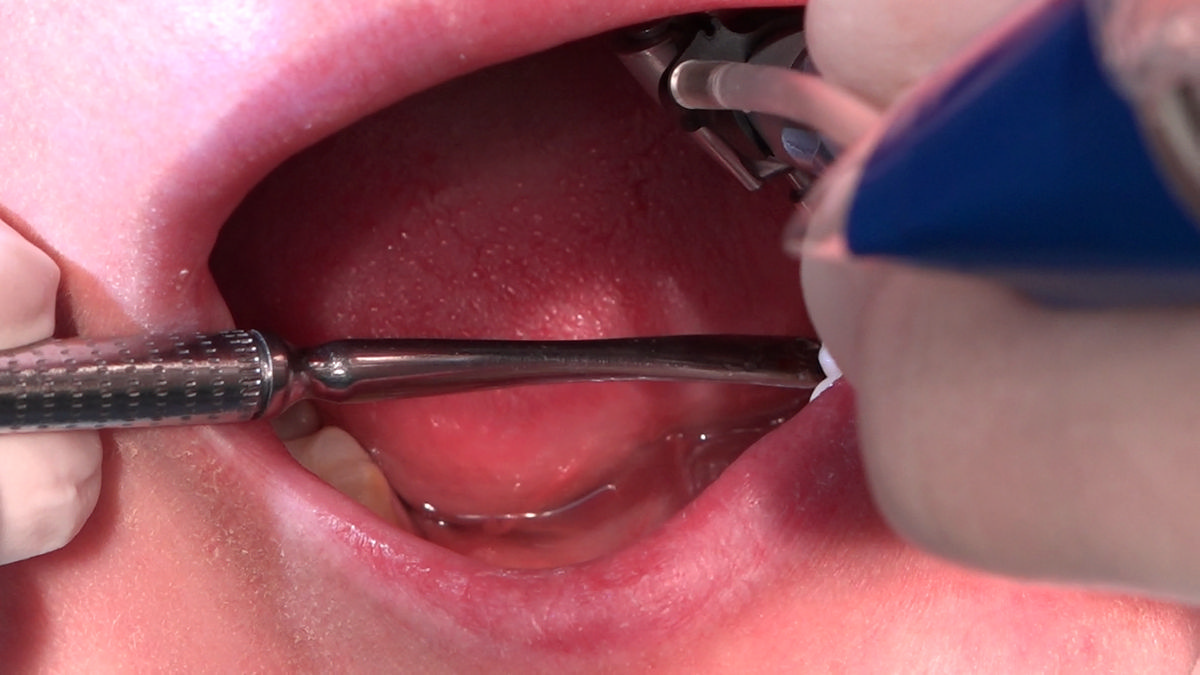

PRACTICULUM IMPLANTOLOGII - SEZON X - SESJA 4 - GRUPA B